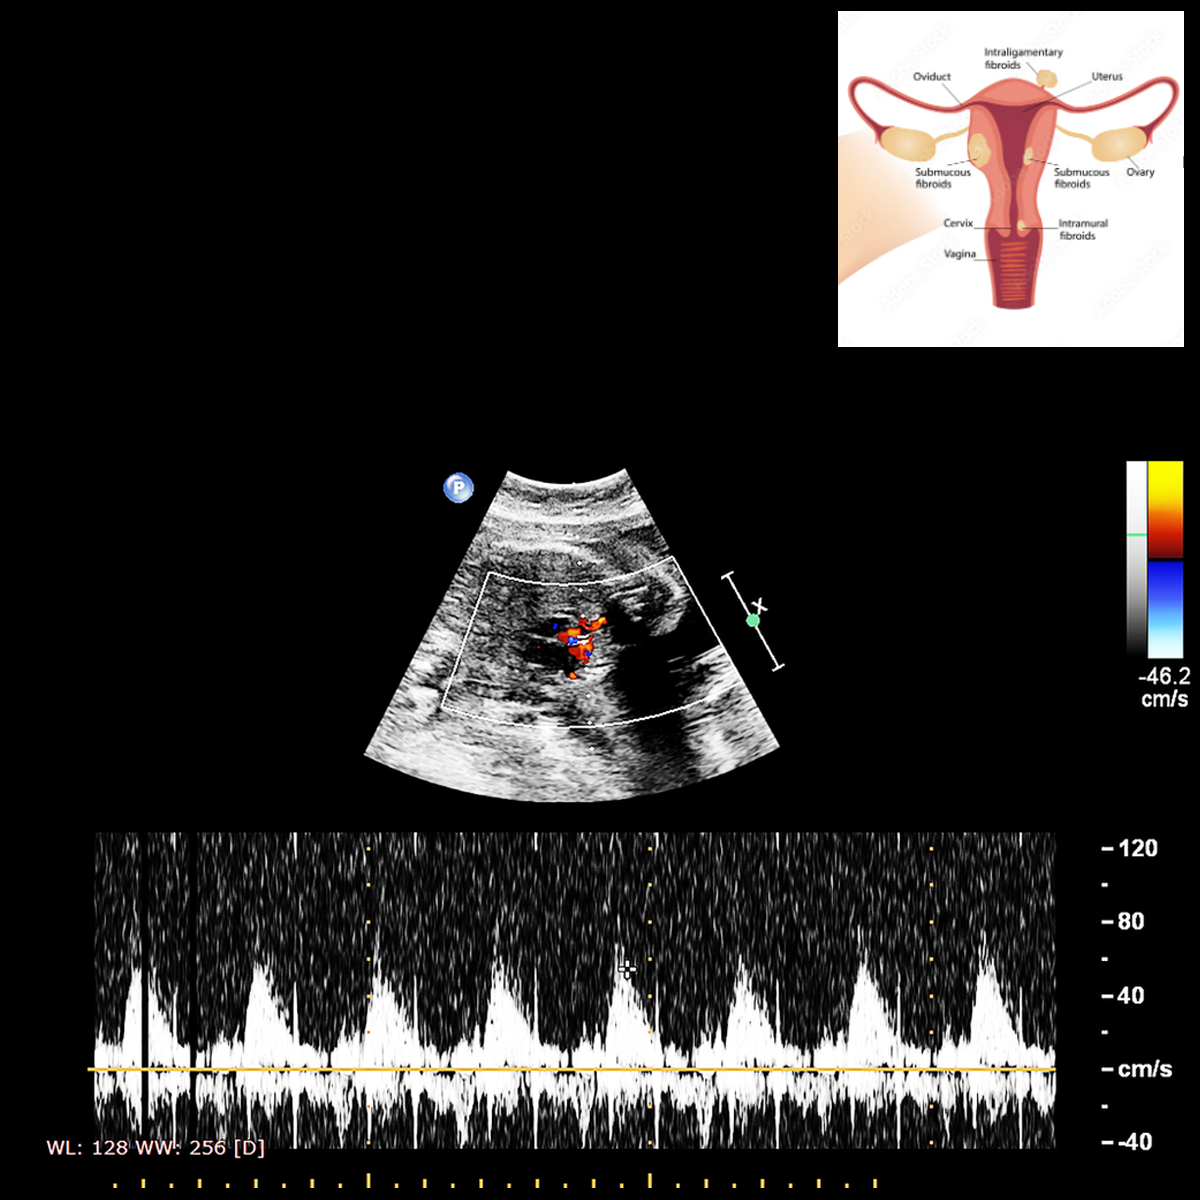

V. Fetal Well Being With Colour Doppler (After 26 weeks):

Done after 26 weeks of gestation, in cases where baby is not growing well, or mother has condition, which can affect baby’s growth, like, diabetes, hypertension, kidney or liver problem, infection.